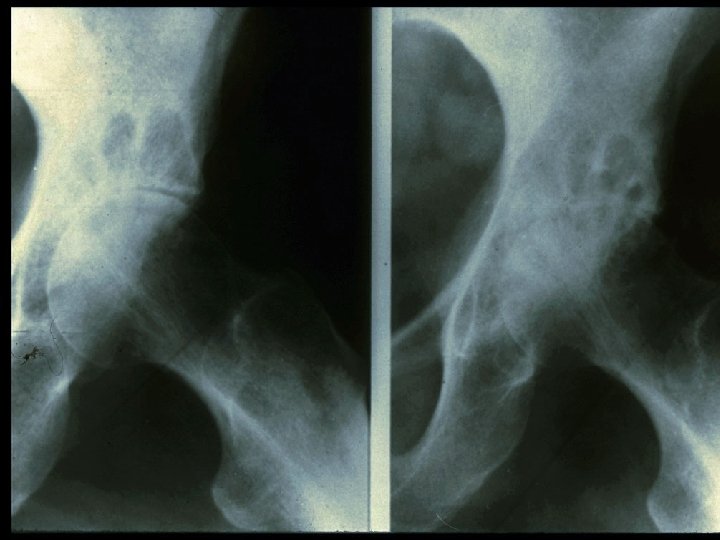

· In addition to steroid therapy, several different disease-modifying drugs were given over the years since diagnosis, including sulfasalazine, oral gold, chloroquine, methotrexate, and TNFinhibitors. · A total of 16 orthopedic operations had been performed including excision of rheumatic nodules, tendon repair, and bilateral knee- and unilateral hip-replacement.

Site of Onset Joint Involvement Mean % of Patients MCP, PIP 91 Wrist 78 Knees 64 Shoulders 65 Ankles 50 Feet 43 Elbows 38 Hips 17

Baseline Evaluation of Patients · Physical Examination - Documentation of actively inflamed joints - Documentation of mechanical joint problems: loss of motion, crepitus, instability, deformity - Documentation of extra-articular manifestations - Optho, cardiac, pulmonary, rash, LAD

Baseline Evaluation of Patients · Radiography - Wrist and hands - Feet - Other symptomatic joints

Sharp Scores of Radiographic Progression Erosion scores · 17 joints of each hand/wrist · 6 joints of each forefoot · Scale: 0– 5; Total score: 0– 230 Joint space narrowing (JSN) scores · 16 joints of each hand/wrist · 5 joints of each forefoot · Scale: 0– 4; Total score: 0– 168 Total Sharp score · Add erosion and JSN scores · Total score: 0– 398 Sharp JT, et al. Arthritis Rheum. 1985; 28: 1326– 1335 van der Heijde DM, et al. J Rheumatol. 1995; 22: 1792– 1796.